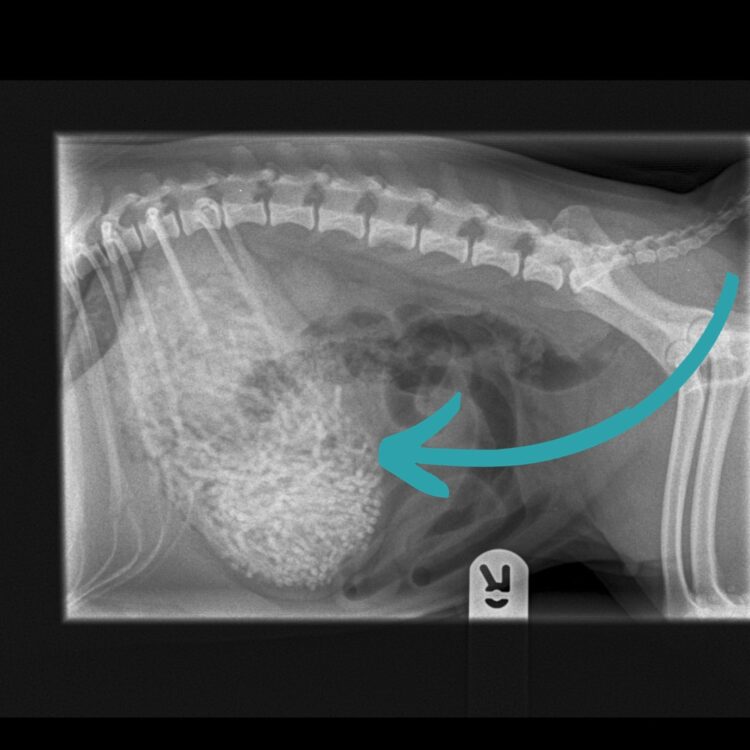

Veterinarka Emily Whitby rekla je da su uklonili 50 do 60 gumica teških 200 grama - Ham ima samo šest kilograma.